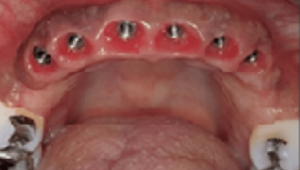

Reabilitação com implantes

Caso Clínico 3 – Prótese fixa sobre implante superior e inferior “Carga imediata